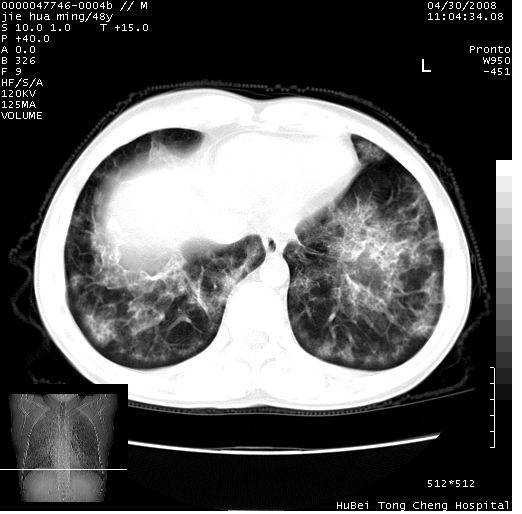

以下是引用dr.yang在2008-5-1 6:25:00的发言:[br]两肺广泛毛玻璃样的片状影,密度不均,边缘欠清,呈碎石路样改变,[br]考虑,1双肺间质性肺炎,2肺泡蛋白沉积症3支气管肺泡癌[br]

以下是引用hhcckk在2008-5-1 8:06:00的发言:[br]支持肺泡蛋白沉积症[br]依据:[br]1、病灶边缘清楚----地图征[br]2、病灶内部小叶间隔或小叶内间隔增厚所形成的网格状影----碎石路样表现[br]3、抗炎治疗无效(炎症抗炎治疗有效)[br]4、纵隔内未见肿大淋巴结(肺泡细胞癌时常有)[br][br]附肺泡蛋白沉积症资料[br][br]肺泡蛋白沉积症(pulmonary alveolar proteinosis)是一种原因不明的以肺泡腔内大量含脂糖蛋白样物质沉积为特征的疾病。[br]病理改变:(1)肺泡和细支气管腔内充满大量含脂糖蛋白样的粘稠物质,该物质为颗粒状或絮状的糖原pas染色阳性的磷脂蛋白。(2)肺泡壁及其间隔无异常改变。胸膜和淋巴结不受累及。(3)晚期可出现弥漫性肺间质纤维化。[br]临床表现:(1)好发年龄30~50岁,男性多于女性,偶见于儿童;(2)主要症状为呼吸困难、咳嗽、低热、消瘦、低氧血症和杵状指等。1/3的患者无症状。(3)实验室检查:痰液或肺泡灌洗液中可找到pas染色阳性颗粒物质。[br]hrct表现:肺泡蛋白沉积症具有特征性改变,即“碎石路样”表现(crazy-paving appearance,cpa)。主要包括(1)斑片状磨玻璃影:指肺野密度朦胧增加,内可见肺血管纹理影,系肺泡腔内充满低密度的磷脂蛋白物质所致。(2)其内部小叶间隔或小叶内间隔增厚所形成的网格状影,为小叶间隔水肿、肺泡壁内淋巴细胞和巨噬细胞浸润以及小叶内淋巴管扩张的缘故。(3)病灶边缘清楚,呈地图样分布于肺野外围或肺门及中央区。[br]

以下是引用zsl6918在2008-5-1 7:35:00的发言:[br]双肺磨玻璃样病变,可见铺碎路石征,病变区与正常区交错。边界清晰。符合肺泡蛋白质沉着征,高分辨扫描会更清楚漂亮。建议临床肺泡灌洗。

以下是引用yangyudong333在2008-5-1 5:36:00的发言:[br][br] 两肺广泛毛玻璃样的片状影,密度不均,边缘欠清,呈碎石路样改变,[br]考虑,1双肺间质性肺炎,2肺泡蛋白沉积症[br]